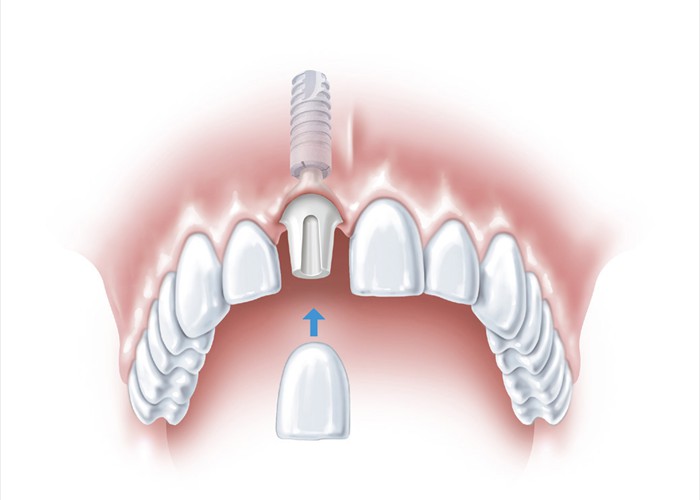

Ein fehlender oberer Frontzahn muss ersetzt werden.

Ein fehlender oberer Frontzahn muss ersetzt werden.

Die beste und zahnschonendste Lösung ist ein Implantat.

Die beste und zahnschonendste Lösung ist ein Implantat.

Hier wird eine Keramikkrone auf das Implantat gesetzt, eine ästhetisch optimale Lösung, bei der die Nachbarzähne nicht beschädigt werden.

Hier wird eine Keramikkrone auf das Implantat gesetzt, eine ästhetisch optimale Lösung, bei der die Nachbarzähne nicht beschädigt werden.